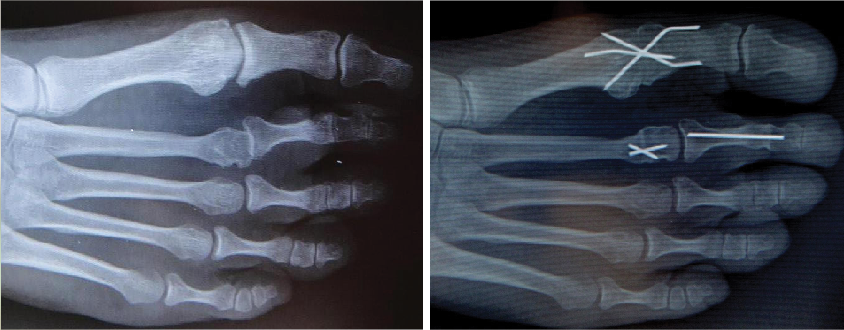

Plain film weightbearing radiographs are the first and often only adjunct exam needed to characterize the clinical diagnosis of plantar plate disruption. The lateral image will indicate a rectus, contracted, subluxed or dislocated joint. Assess arthritis within the joint as longstanding deformities can demonstrate bony erosion of the dorsal aspect of the metatarsal head and/or phalangeal base. One can best evaluate transverse plane deformity on the dorsal plantar image as well as any associated first ray or lesser ray deformities. Plain film radiography also provides the baseline for future comparison regarding progression of the deformity as well as assessing post-op healing.

In most cases, there is a hammertoe contracture and I perform a proximal interphalangeal joint arthrodesis with a buried K-wire (in slight flexion so as not to be too straight). If the toe is still unable to touch the ground, then we open the MPJ dorsally and perform an open Z-plasty of the extensor digitorum longus tendon (and usually section the extensor brevis tendon). If reduction is inadequate, we then perform a dorsal MPJ capsulotomy. If the toe is medially deviated, we also perform a medial capsulotomy and vice versa for a laterally deviated toe (much less common). If reduction is inadequate, then we address the plantar plate.

To that en

d, we utilize a transverse, translocating, Hohmann-type osteotomy detailed by Behrens and Goforth.5,6 This procedure enables the surgeon to structurally move the metatarsal back under the toe, similar to how we correct a bunion (but in the opposite direction). This is a vertical metaphyseal osteotomy in which the metatarsal head shifts one-fourth to one-third the width of the bone. Slight angulation of the cut can achieve a moderate amount of shortening should one desire this. Surgeons can use crossing (1.1 mm diameter) threaded K-wires for fixation. Performing additional soft tissue balancing can release contractures (medial capsule/collateral ligaments) and tighten the weak structures (lateral capsule).